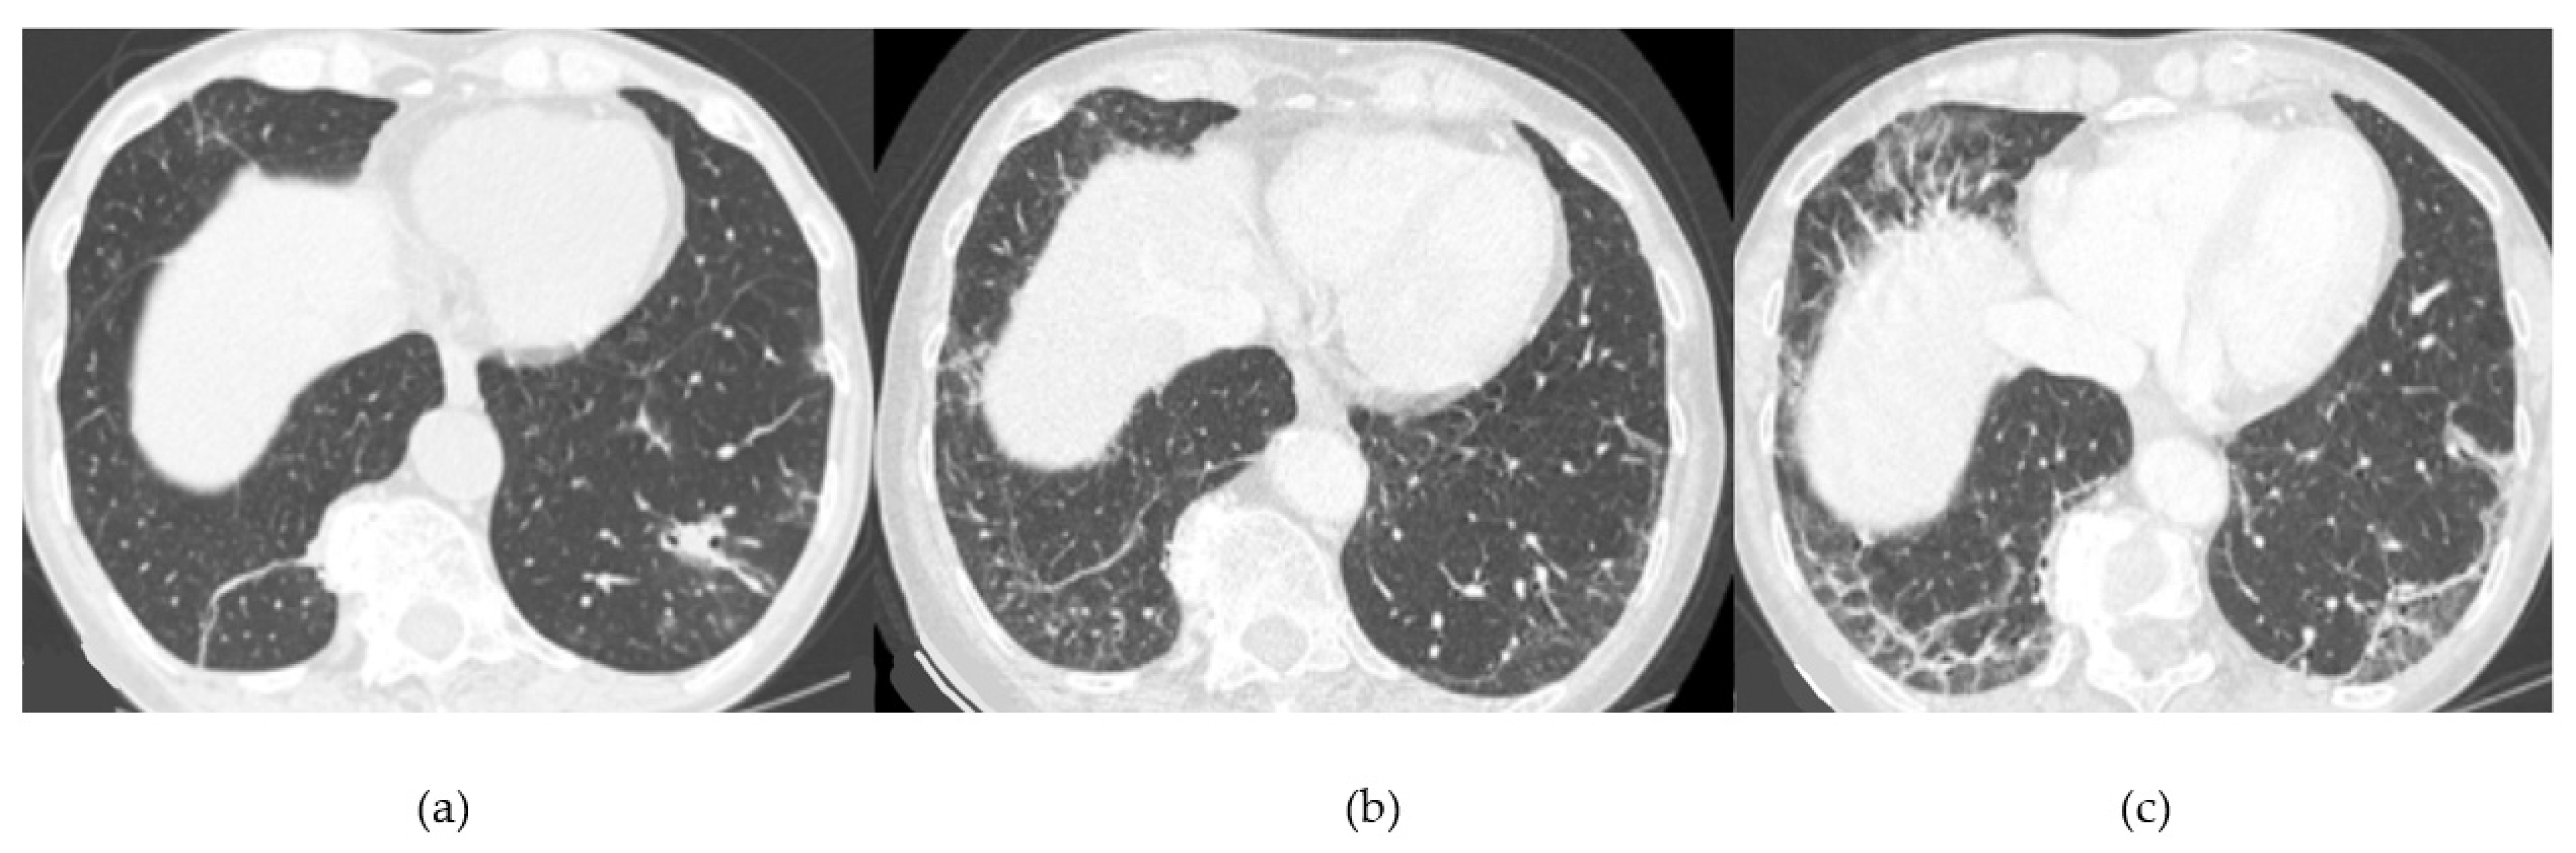

- Acute or rapidly progressive ILD (acute interstitial pneumonia and radiological evidence of acute respiratory distress syndrome (ARDS) due to diffuse alveolar damage) [44];

Acute Type

| Lesions | GGO, reticulations, consolidations | consolidations, GGOs | |

| Distribution | Homogeneous; lower lung lobes, along bronchovascular bundles and lung periphery; loss of volume of lower lobes | Patchy; peripheral lower lobes or along the bronchovascular bundles | |

| CT pattern | NSIP OP NSIP-OP UIP DAD-unclassifiable | 50% 20% 25% 10% +/− | 20% 50% 25% <5% ++ |